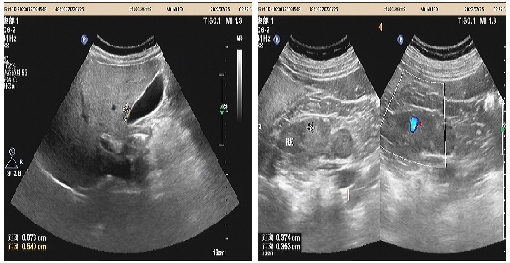

05、**女士,60岁

于2023年7月25日在邯郸仁泰北区体检,腹部彩超检查提示:右肾皮质部内见大小2.0*2.2cm低回声,边界尚清晰、形态欠规整,周边可见少量血流信号。诊断:右肾低回声;双肾CT检查考虑:肾占位性病变,建议客户肾增强CT检查。2023年8月1日跟踪回访,客户家属告知,增强CT考虑右肾占位,已住院准备手术治疗。

09、**女士,56岁

于2023年7月25日在银川仁泰体检部体检,腹部彩超检查提示:左侧肾上腺区可见一低回声团,大小约37x34mm,边界欠清,内回声不均。考虑:左侧肾上腺区占位性病变(性质待定)。建议客户到综合医院专科进一步检查。2023年8月2日跟踪回访,已在当地某三甲医院住院,准备手术。